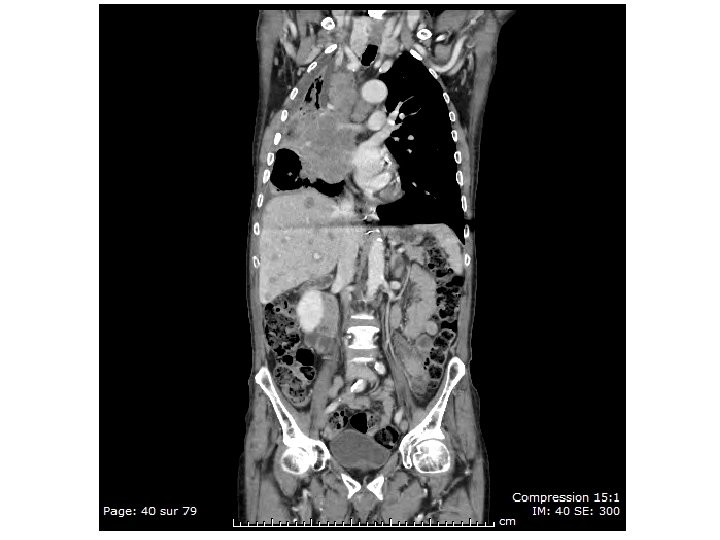

Abdelkader S… - 31/12/29 • Antécédents – HTA, AOMI, ACFA sous AVK – BPCO sur emphysème, pneumothorax en 2002 (lobectomie supérieure droite) – néphrectomie droite post-traumatique en 1970. – endartériectomie fémorale commune et profonde, angioplastiestenting iliaque externe droit le 04/10/2012 • Anamnèse – anorexie, asthénie depuis un mois et demi, amaigrissement de 8 kg en 4 -5 mois, anémie 8, 2 g/dl – douleur lombaire droite depuis 2 mois, douleurs 2 jambes D>G

Abdelkader S… - 31/12/29 • Examen clinique – Douleur lombaire droite++ – Douleurs des jambes particulièrement à droite, notamment lors de la mobilisation. – Signe de Lasègue bilatéral, signe de la sonnette paravertébral droit. – Escarre du talon droit • Biologie – CRP : 271 mg/L, albumine 20 g/l – Phosphatases alcalines : 771 UI/L, ASAT : 107 UI/L , ALAT : 12 UI/L, GGT: 22 UI/L – Leucocytes : 10. 63 giga/L , Hémoglobine : 7. 5 g/d. L, VGM : 84. 3 fl, Plaquettes : 227 giga/L – Calcémie 2, 29 mmol/l – Calcémie corrigée 2, 79 mmol/l

Abdelkader S… - 31/12/29 • Scanner TAP : pas de formation néoplasique • Scanner lombaire : tassements • Scintigraphie osseuse : lésions ostéocondensantes intéressant le squelette axial et périphérique évoquant en premier lieu une néoplasie …X • PSA à 620 ng/ml